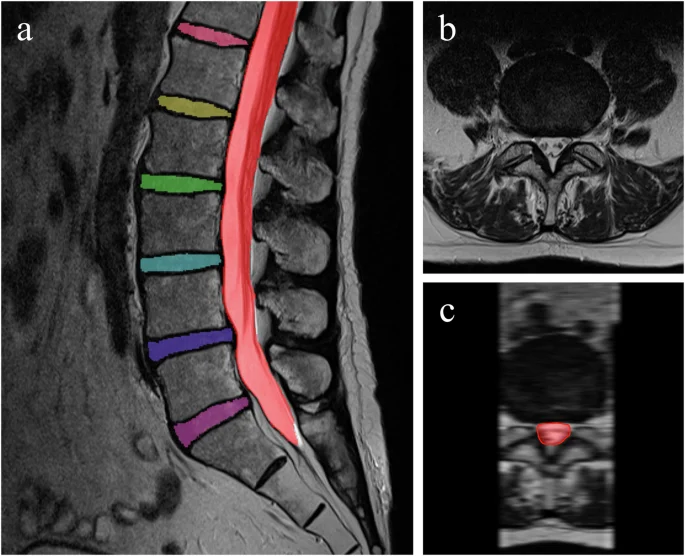

- MRI:最も確定診断に有用ではありますが、診察との整合性が大事です。

- MRIで観察すると飛び出したヘルニアが縮小・消失することは非常に多い。

MRI(非常に重要)

- 新しい圧迫骨折かどうかが明確に分かる

- 骨の中の浮腫(むくみ)が明るく写る

- 多発の確認がしやすい

脊柱管狭窄症は脊髄や神経根が通る「脊柱管」が狭くなり、神経が圧迫されて起きる症状の総称です。原因は加齢による椎間板の変性、椎間関節(ファセット)の肥厚、靭帯(黄色靭帯)の肥厚、骨棘などの変化が主です。先天的に狭いタイプもあります。画像(MRI)で脊柱管の狭小化が確認できますが、画像で狭いところがある=必ず症状が出るとは限りません(臨床所見との照合が重要です)。

- 画像検査:レントゲンとMRIが最も有用。CTを追加することもあります。しかし重要なことは、これらの画像検査は診断の参考程度のものであり、治療方法の判断は総合評価にて行います。